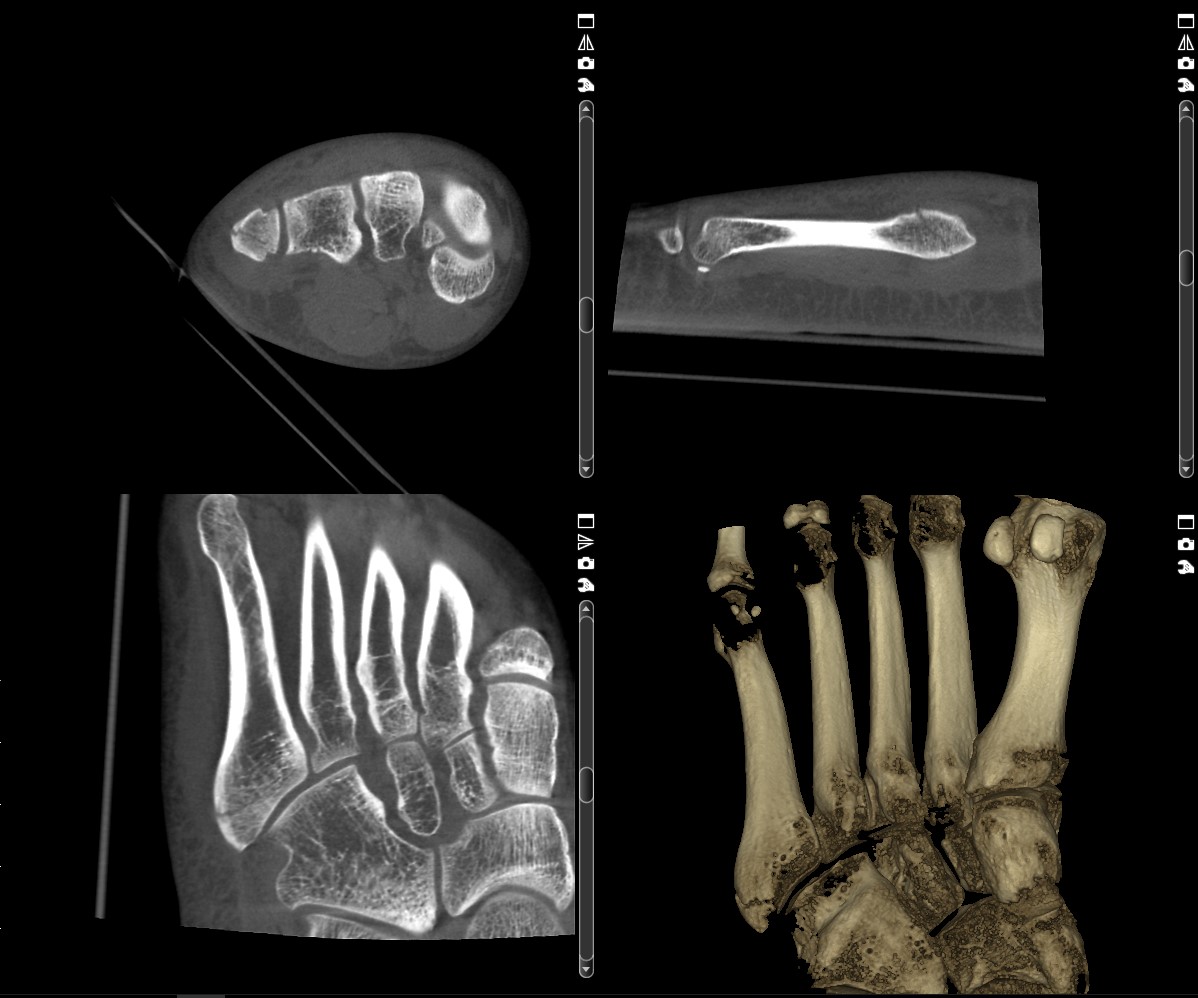

- Genaue Lokalisation freier Gelenkkörper,

- Feinste Veränderungen an den kleinen Knochen der Finger und Zehengelenke werden sichtbar,